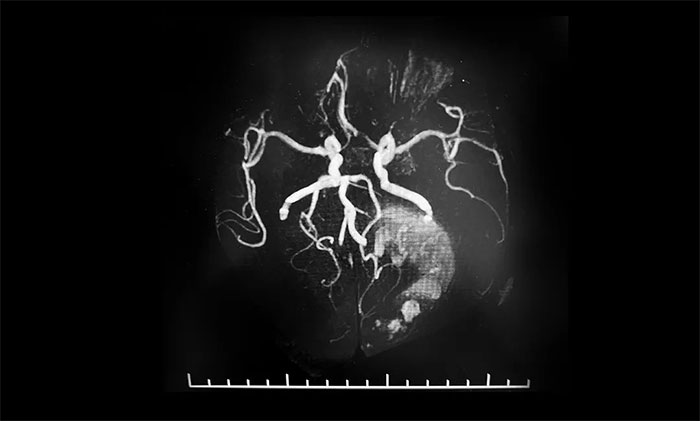

▲ 术前MRA,了解肿瘤供血情况

术前,潘仁龙主任给予患者脱水剂、白蛋白、甘露醇等药物治疗,患者病情逐渐稳定,可以睁眼,身体相关指标达到手术条件。为了进一步降低手术风险,李士其教授等专家团队进行了详细的术前准备,包括手术设计、切口大小设计、手术备血等。同时,术前进行了磁共振血管成像,详细了解肿瘤供血情况,确保手术可控,万无一失。